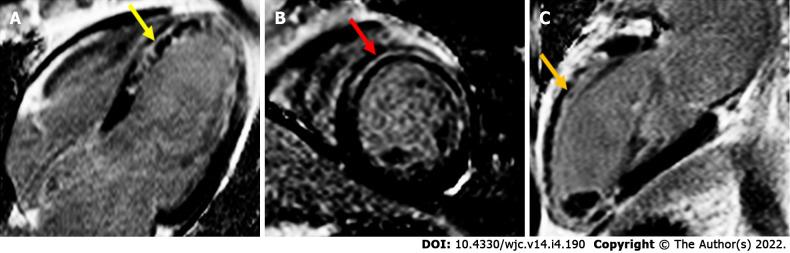

Cardiac magnetic resonance imaging (MRI) is an evolving technology, proving to be a highly accurate tool for quantitative assessment. Most recently, it has been increasingly used in the diagnostic and prognostic evaluation of conditions involving an elevation in troponin or troponinemia. Although an elevation in troponin is a nonspecific marker of myocardial tissue damage, it is a frequently ordered investigation leaving many patients without a specific diagnosis. Fortunately, the advent of newer cardiac MRI protocols can provide additional information. In this review, we discuss several conditions associated with an elevation in troponin such as myocardial infarction, myocarditis, Takotsubo cardiomyopathy, coronavirus disease 2019 related cardiac dysfunction and athlete's heart syndrome.

心脏磁共振成像(MRI)是一项不断发展的技术,已被证明是一种用于定量评估的高度准确的工具。最近,它越来越多地用于涉及肌钙蛋白升高或肌钙蛋白血症的疾病的诊断和预后评估。尽管肌钙蛋白升高是心肌组织损伤的非特异性标志物,但它是一项经常进行的检查,导致许多患者无法得到明确诊断。幸运的是,更新的心脏MRI检查方案的出现可以提供更多信息。在这篇综述中,我们讨论了几种与肌钙蛋白升高相关的疾病,如心肌梗死、心肌炎、Takotsubo心肌病、2019冠状病毒病相关的心功能障碍和运动员心脏综合征。